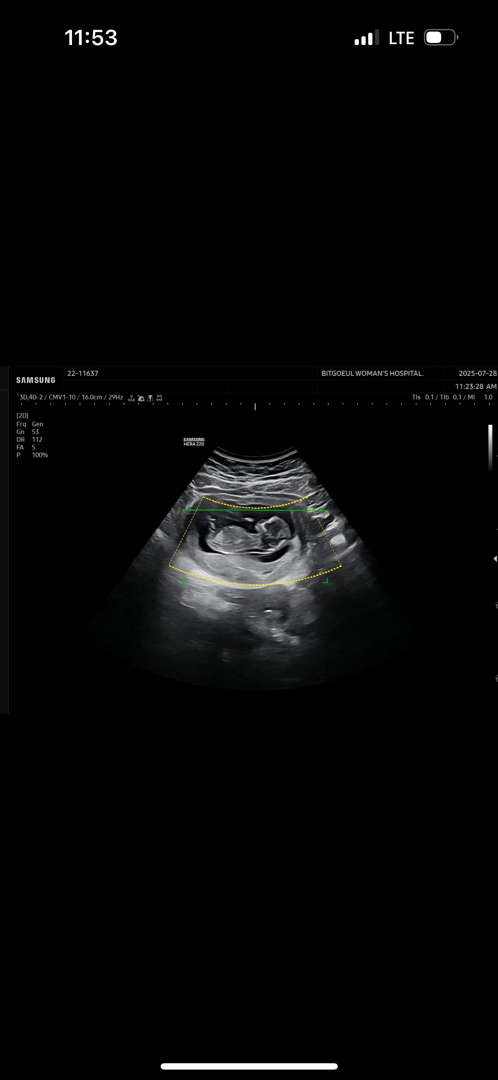

각도법!!

어떤가요? 모르겟어요 전혀 ㅋㅋㅋ